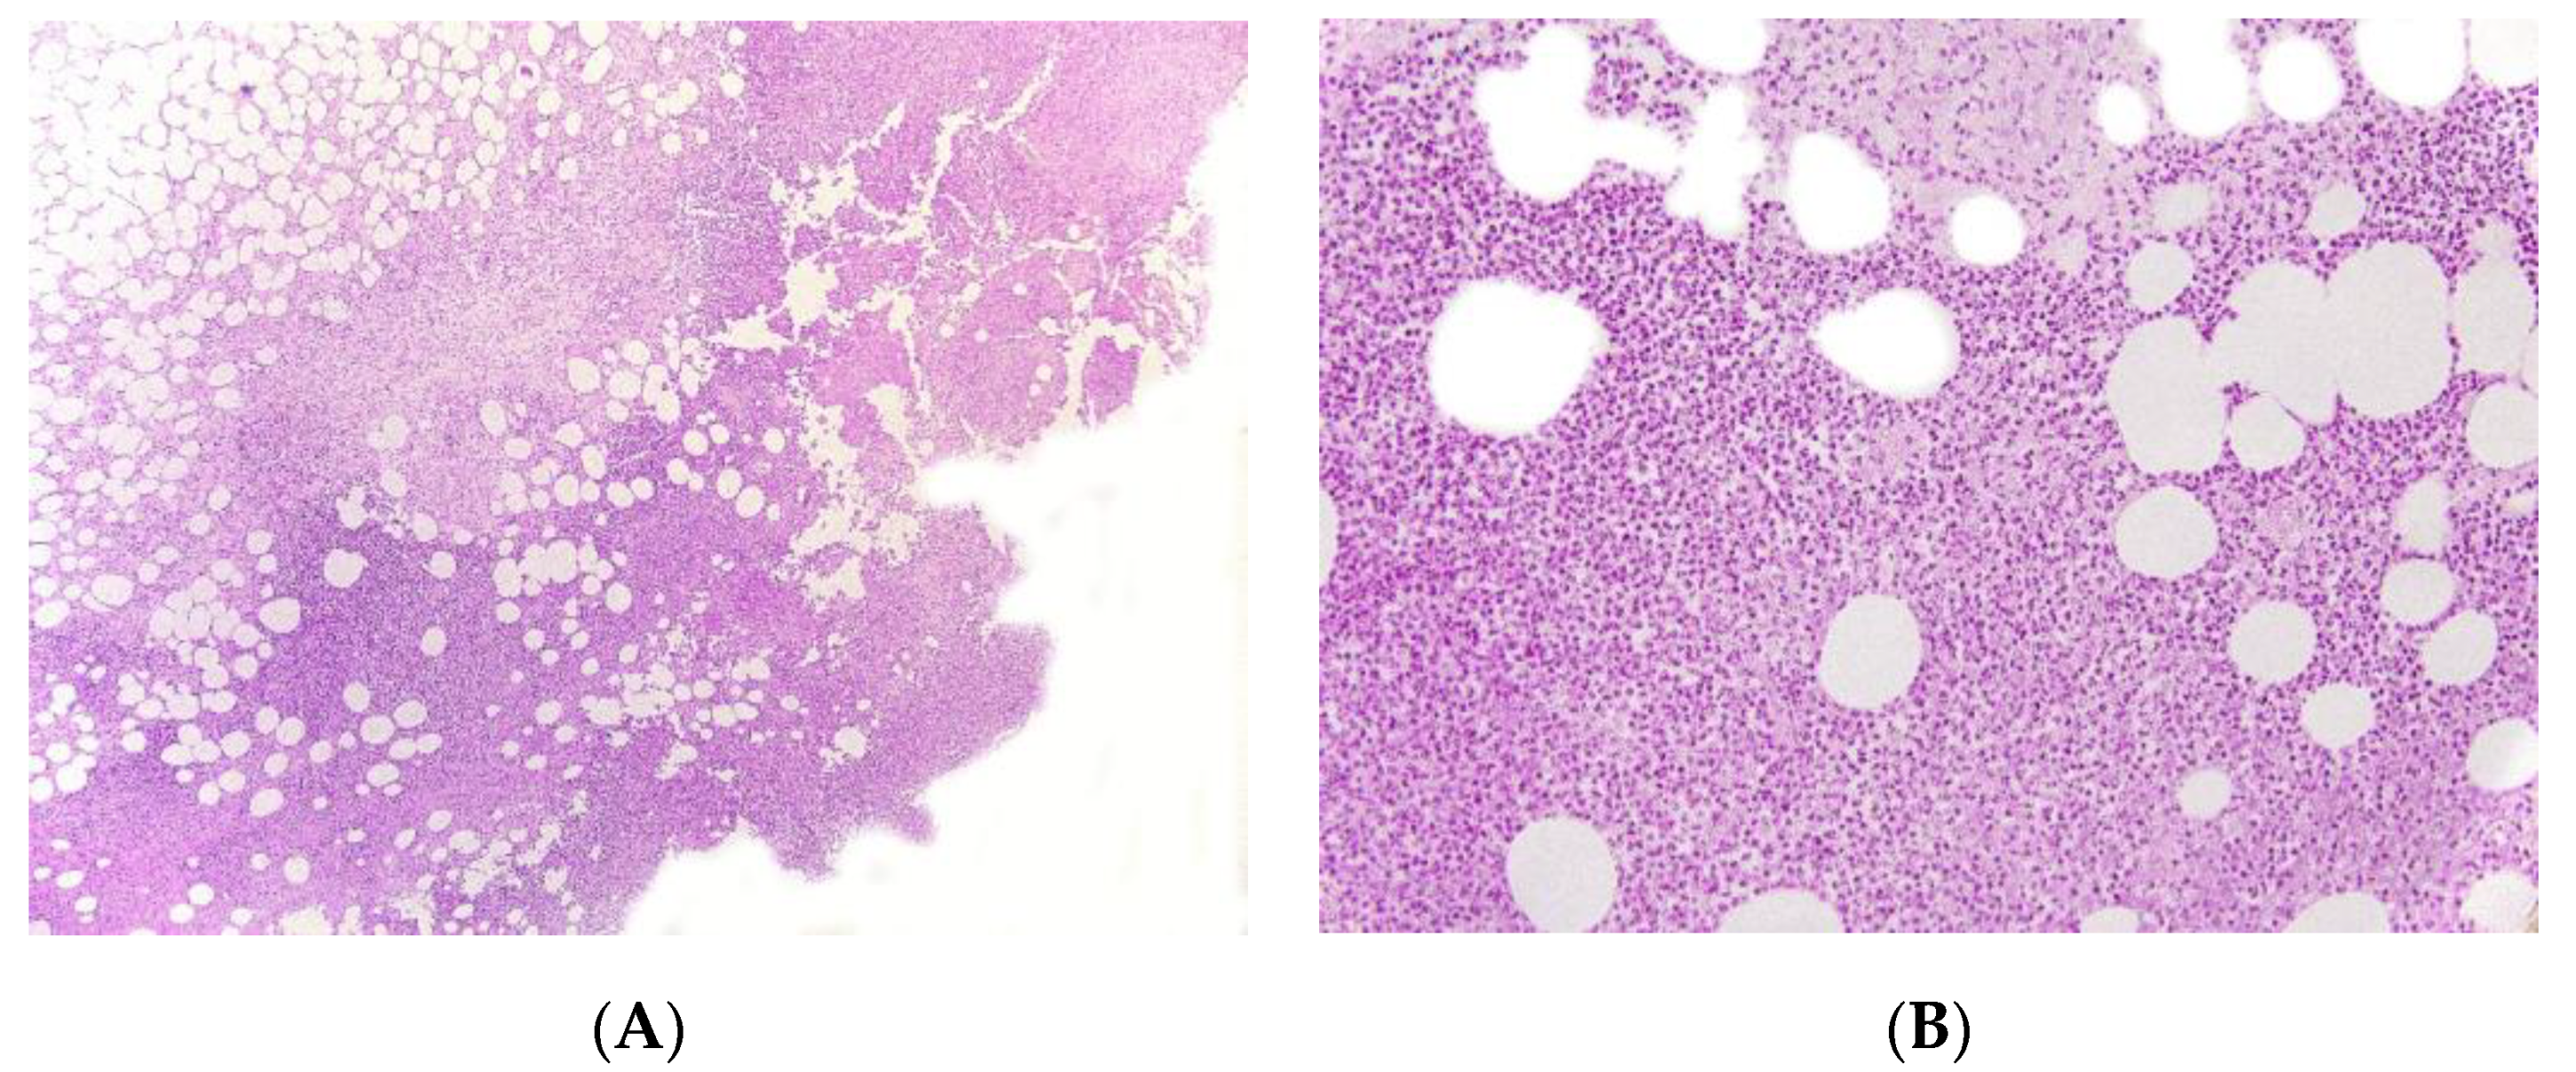

2.4. Autoinflammatory Diseases

Early-onset panniculitis with systemic inflammation had been reported in cases of autoinflammatory diseases with or without an associated immunodeficiency [13,14]. Most cases have variable, non-specific histopathologic features: lobular or septal panniculitis with a mixture of cells or with a predominance of neutrophils or lymphocytes (Figure 3 and Figure 4). However, the histopathologic features can sometimes have diagnostic value, such as the granulomatous infiltrate characteristic of Blau syndrome (BS) or the polyarteritis-nodosa-like vasculitis in deficiency of adenosine deaminase 2 (DADA2). The presence of early-onset panniculitis with systemic inflammation should prompt the physician to screen for autoinflammatory disorders.

Figure 4.

Panniculitis associated with inherited immunodeficiency. (A) Lobular panniculitis with dense neutrophilic infiltrate replacing part of the subcutis (original magnification ×80). (B) Closer view of showing entrapped adipocytes within the neutrophilic infiltrate (original magnification ×200).